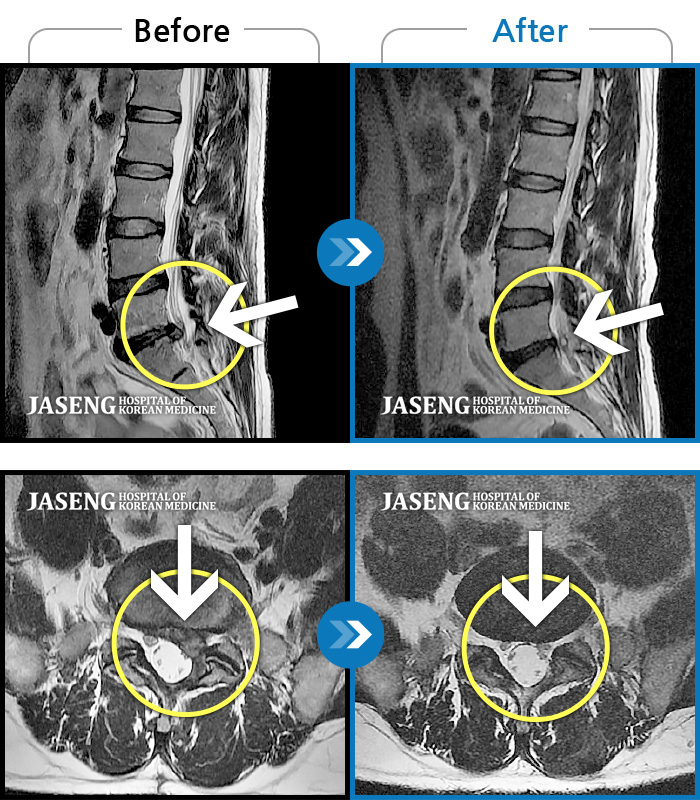

MRI ũ ʸ Ȯϼ.